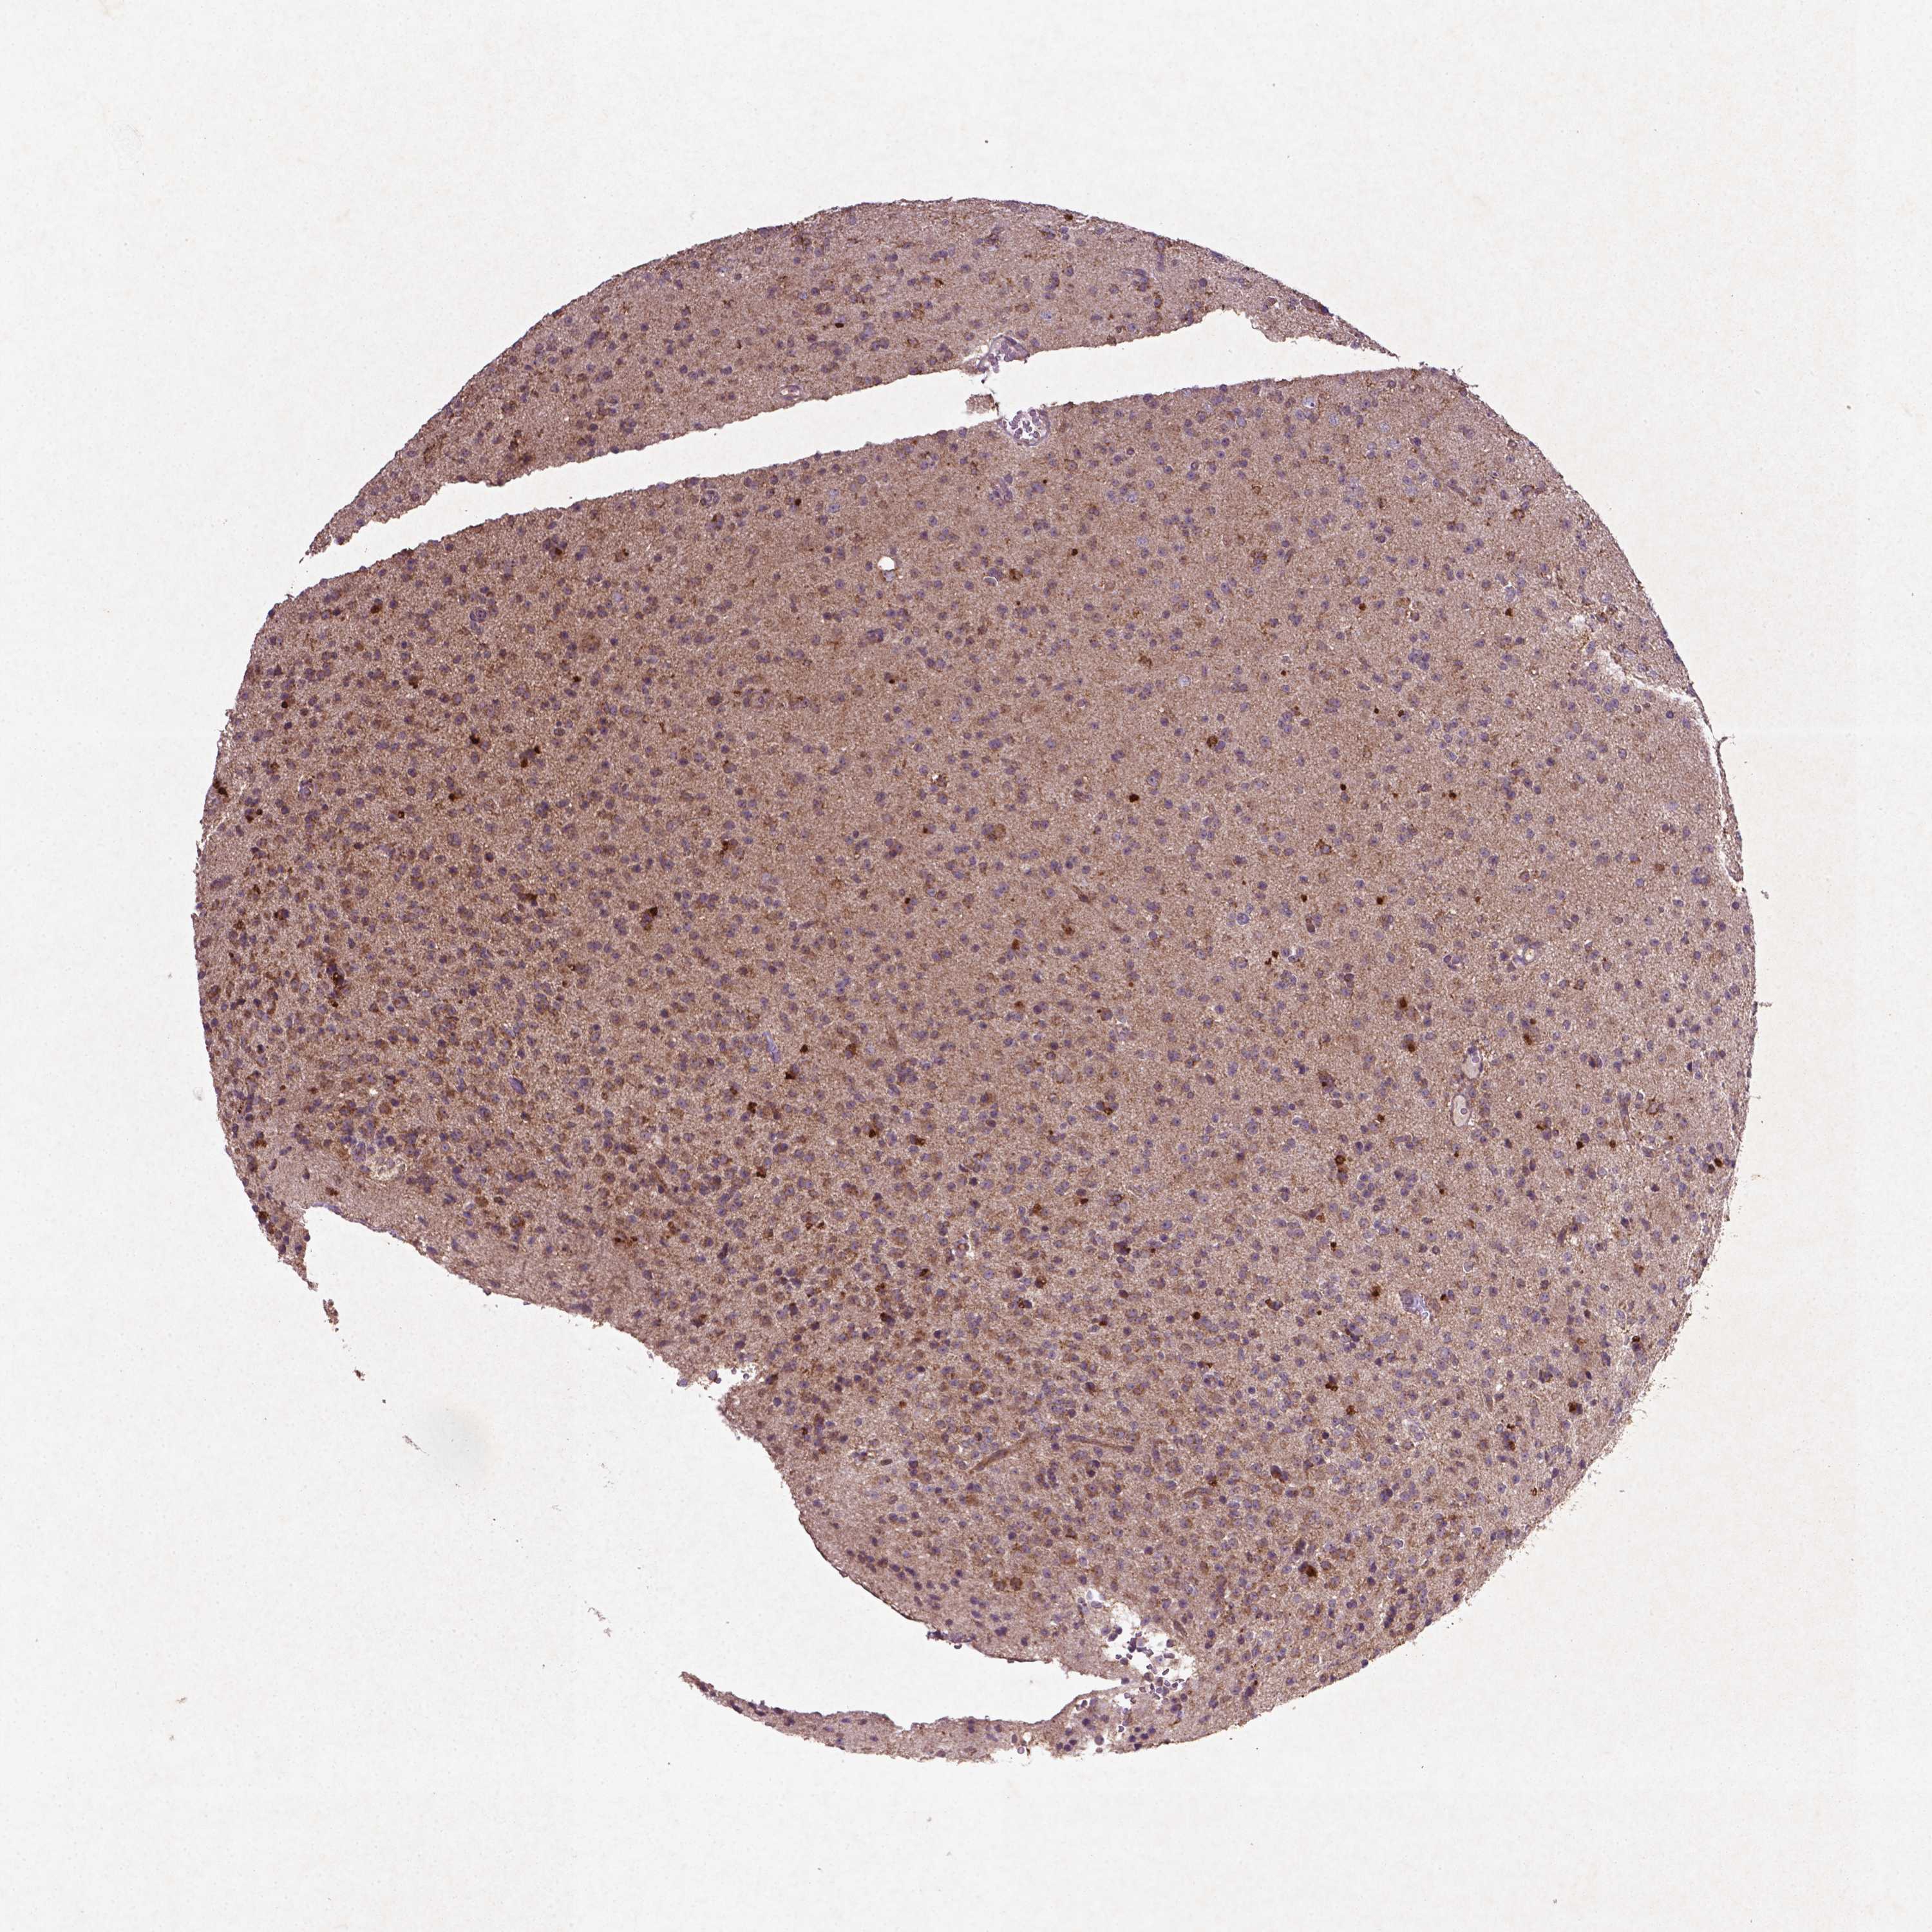

GLIOMA - Protein expressioni

A mouse-over function shows sample information and annotation data. Click on an image to view it in a full screen mode. Samples can be filtered based on level of antibody staining by selecting one or several of the following categories: high, medium, low and not detected. The assay and annotation is described here.

Note that samples used for immunohistochemistry by the Human Protein Atlas do not correspond to samples in the TCGA dataset.

Antibody stainingi

Antibody staining in the annotated cell types in the current human tissue is reported as not detected, low, medium, or high, based on conventional immunohistochemistry profiling in selected tissues. This score is based on the combination of the staining intensity and fraction of stained cells.

Each image is clickable and will lead to virtual microscopy that enables deeper exploration of all samples and also displays staining intensity scores, fraction scores and subcellular localization as well as patient and tissue information for each sample.

CAB069425

CAB080053

CAB080065

CAB080070

CAB080081

CAB080095

CAB080097

Staining

High

Medium

Low

Not detected

Intensity

Strong

Moderate

Weak

Negative

Quantity

>75%

75%-25%

<25%

None

Location

Nuclear

Cytoplasmic/membranous

Cytoplasmic/membranous,nuclear

Glioma, malignant, Low grade

Glioma, malignant, High grade

Glioma, malignant, NOS